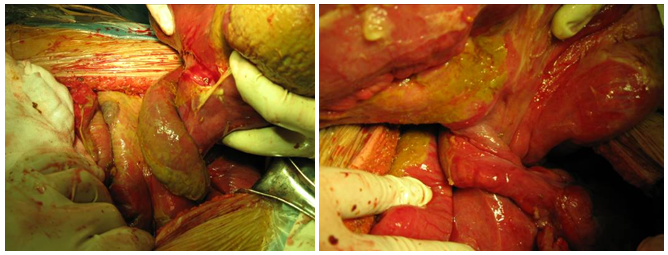

On physical examination, the female patient was found to have a distended, painful abdomen and weak bowel sounds with two operation scars at the right upper quadrant abdomen. She was afebrile and had a blood pressure of 100/70 mmHg, The Computed Tomography scan in our hospital demonstrated ileus with abdominal intestinal canal obviously effusion plot gas, intrahepatic bile ducts dilation and pneumobilia, hepatolithiasis, seroperitoneum, intestinal wall edema, with the possibility of stone obstruction in the small intestine(Figure 1). The gastrointestinal radiography using iohexol demonstrated duodenal diverticulum, intrahepatic bile ducts pneumobilia and ileus. On laparotomy, two large (3cm) gallstones were identified obstructing the distal ileum and two perforations of size 7-8 mm and 2-3mm respectively with approximately 1meter of gangrenous patches in the adjacent bowel (Figure 3). The ileum 20 cm from the ileocecal junction twisted for 540°C (Figure 2). Resection anastomosis was done. The patient is recouping well postoperatively.

Figure 1 Computed Tomography scan revealed ileus, intrahepatic bile ducts dilation and pneumobilia, hepatolithiasis, seroperitoneum, Intestinal wall edema, stone obstruction in the small intestine.

Figure 2 Intraoperative picture showing the ileum of 20cm from the ileocecal junction volvulus of 540°C.

Figure 3 Intraoperative picture showing two large (3cm) gallstones obstructing the distal ileum and two perforations of size 7-8 mm and 2-3mm respectively.